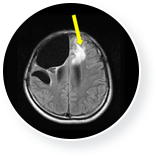

• 뇌종양 치료 전 이미지

뇌종양 치료 전